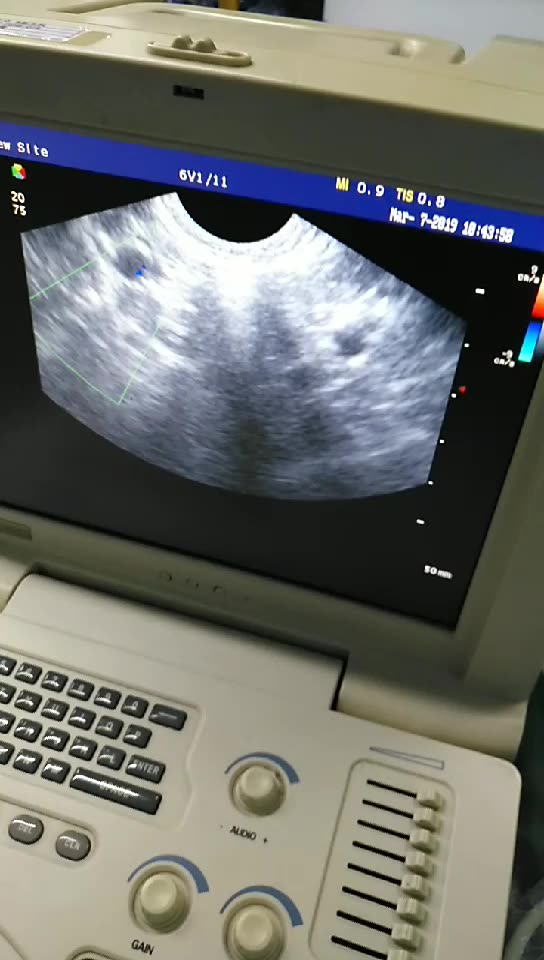

Медицинская Техника: УЗИ с Ge Voluson 730 Expert

Раздел: Фотозарисовки